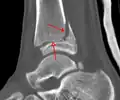

Une fracture triplane de la cheville vue par TDM

CT

Les tomodensitogrammes peuvent être indiqués en cas de risque de fracture fragmentée ou de fracture impliquant la surface articulaire[9]. Cette imagerie peut être utilisée pour la planification chirurgicale.

- Les fractures triplanes, un type particulier de fracture qui implique le squelette immature[13].